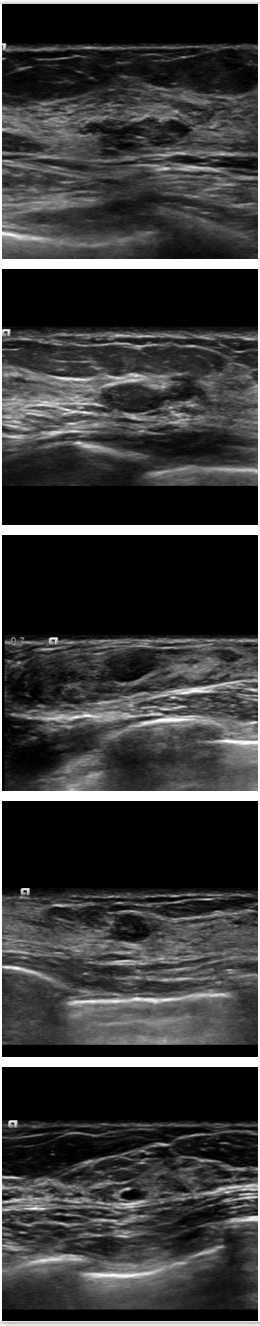

Refer to caption

Figure 11: Comparison among SPCGAN, GAN and FCN(ResNet) in a TOSHIBA image. (a) shows original image of benign lesions, (b) shows the manual annotation, (c) shows the result of SPCGAN ,(d) shows the result of GAN , and (e) shows results from FCN(ResNet).

To explore the performance of SPCGAN on the segmentation quality with test data from different manufactures, we collected 30 BUS images of breast disease scanned from TOSHIBA Ultrasound System and applied our model which was trained on SIEMENS images only.

From Table 3, we can observe that the difference between DSC values of SPCGAN and FCN(ResNet) was not statistically significant (p=0.14 with paired t-test). The example given in Fig. 11 corresponds to a breast cancer with the ill-defined boundary. They are both very robust but the mean DSC from SPCGAN is still higher.